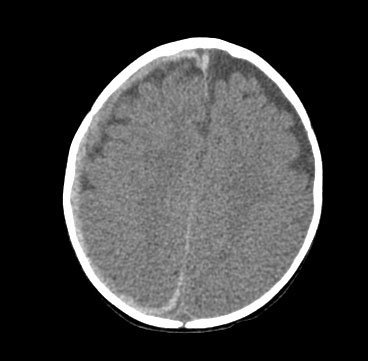

[Figure caption and citation for the preceding image starts]: CT findings in fatal abusive head trauma often reveal significant brain oedema with loss of grey-white differentiation and effacement of the ventricles. Subdural blood is often difficult to appreciate in such casesFrom the personal collection of Alice Newton, MD; used with permission [Citation ends].